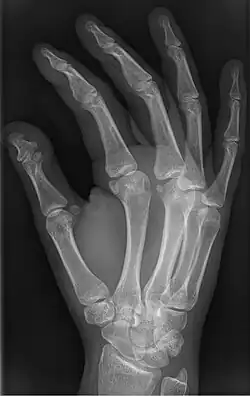

| Brachyphalangy of the thumb's distal phalanx, also known as brachydactyly type D, with otherwise normal phalanges of the 2nd-5th digits | |

| Symptoms | Having a phalange(s) shorter than average |

Brachyphalangy is a condition in which one or more of the phalanges of the fingers and toes are smaller than normal.[1]

This condition is caused by either fusion or early closure of the phalange's growth plate. One example is brachydactyly type D, which is caused by an early closure of the thumb's distal phalange, leading to a congenitally short thumb with a similarly short and wide thumb nail.